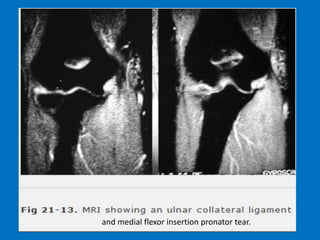

Ulnar collateral ligament (UCL) injury refers

to a sprain, partial tear or complete tear of

the ligament that traverses the inside (or

medial side) of the elbow. The UCL is the

primary stabilizer of the elbow and plays an

important role in throwing and hitting

sports, such as baseball, football and tennis.

Additional findings: Strain or rupture of the

common flexor tendon, ulnar neuropathy,

ulnar traction spurring or heterotopic

ossification of the soft tissues

and medial flexor insertion pronator tear.